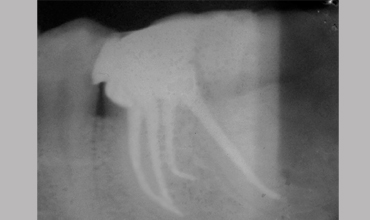

Management Of Radix

Management Of Radix Entomolaris In Mandibular First Molar